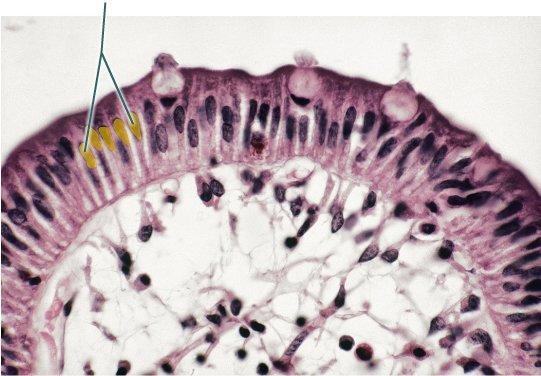

Which epithelial type is highlighted?

simple cuboidal epithelium

pseudostratified columnar epithelium

simple columnar epithelium

simple squamous epithelium

simple columnar epithelium

Which structures are highlighted?

cilia

microvilli

goblet cells

nuclei

microvilli

Which epithelial type is highlighted?

stratified squamous epithelium

transitional epithelium

pseudostratified columnar epithelium

simple columnar epithelium

pseudostratified columnar epithelium

Which structures are highlighted?

goblet cells

pseudostratified columnar epithelium

cilia

microvilli

cilia